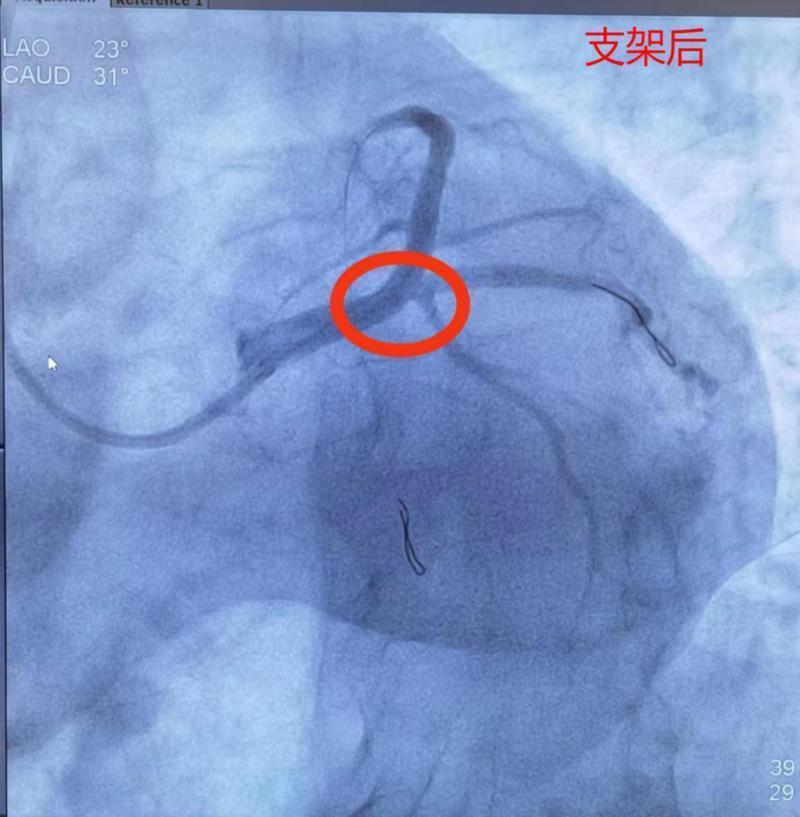

在急诊科、心内科、介入室众多医护人员的共同努力下,患者闭塞的回旋支被开通。从进入导管室到手术结束约耗时40分钟,禾正医院首例急性ST段抬高型心肌梗死急诊手术顺利完成!

术后心电图抬高的ST段回落,未见病理性Q波。由于患者开通堵塞血管及时,坏死的心肌细胞较少,最大程度保护了患者心脏功能,避免日后心力衰竭的发生。术后陆先生恢复良好,于8月16日康复出院。

紧急与家属沟通,在征得患者家属同意后,17:10汤先生由急诊科送入导管室行紧急PCI术。冠脉造影显示:左主于末端85%-90%重度狭窄,前降支开口90%重度狭窄,局部可见明显血栓影。从进入导管室到手术结束,前后约45分钟,门球时间50分钟。术后汤先生生命体征平稳、转危为安。

对于急性心肌梗死患者来说:“时间就是心肌、时间就是生命!”急诊造影并支架植入治疗(PCI)是目前救治这种类型急性心肌梗死的首选治疗方式,并且越早治疗,获益越大。PCI能够尽快开通闭塞段血管,缩小心肌梗死面积,挽救缺血的心肌细胞,拯救生命,对提高患者存活率、降低死亡率和致残率都有重要意义。